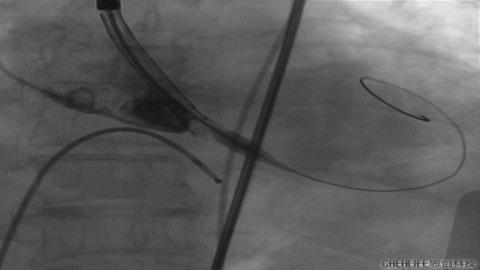

此例患者大横位Type0型二叶瓣,瓣环径23.1,LVOT22.6,Stj35.9,左冠高度11.8,右冠19.5,术前根据总体结构使用20MM球囊预扩,抓捕器辅助瓣膜通过横位结构跨瓣,术前预装VenusA23号瓣膜。

发生瓣叶切割,无窦侧瓣叶切割,Type0结构形变为类三叶瓣结构。